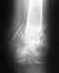

Сращения действительно не видно. Поскольку кровоснабжение отломков не очень хорошее, пластина или винты сломаются раньше, чем срастется. И в качестве первой операции, и второй, да и сейчас, оптимально было бы сделать закрытый внутрикостный остеосинтез стержнем с блокированием. Если стержень использован достаточно мощный, можно ходить без ограничений нагрузки сразу после операции, и усталостного запаса прочности хватает до сращения. Где Вы проходите лечение?